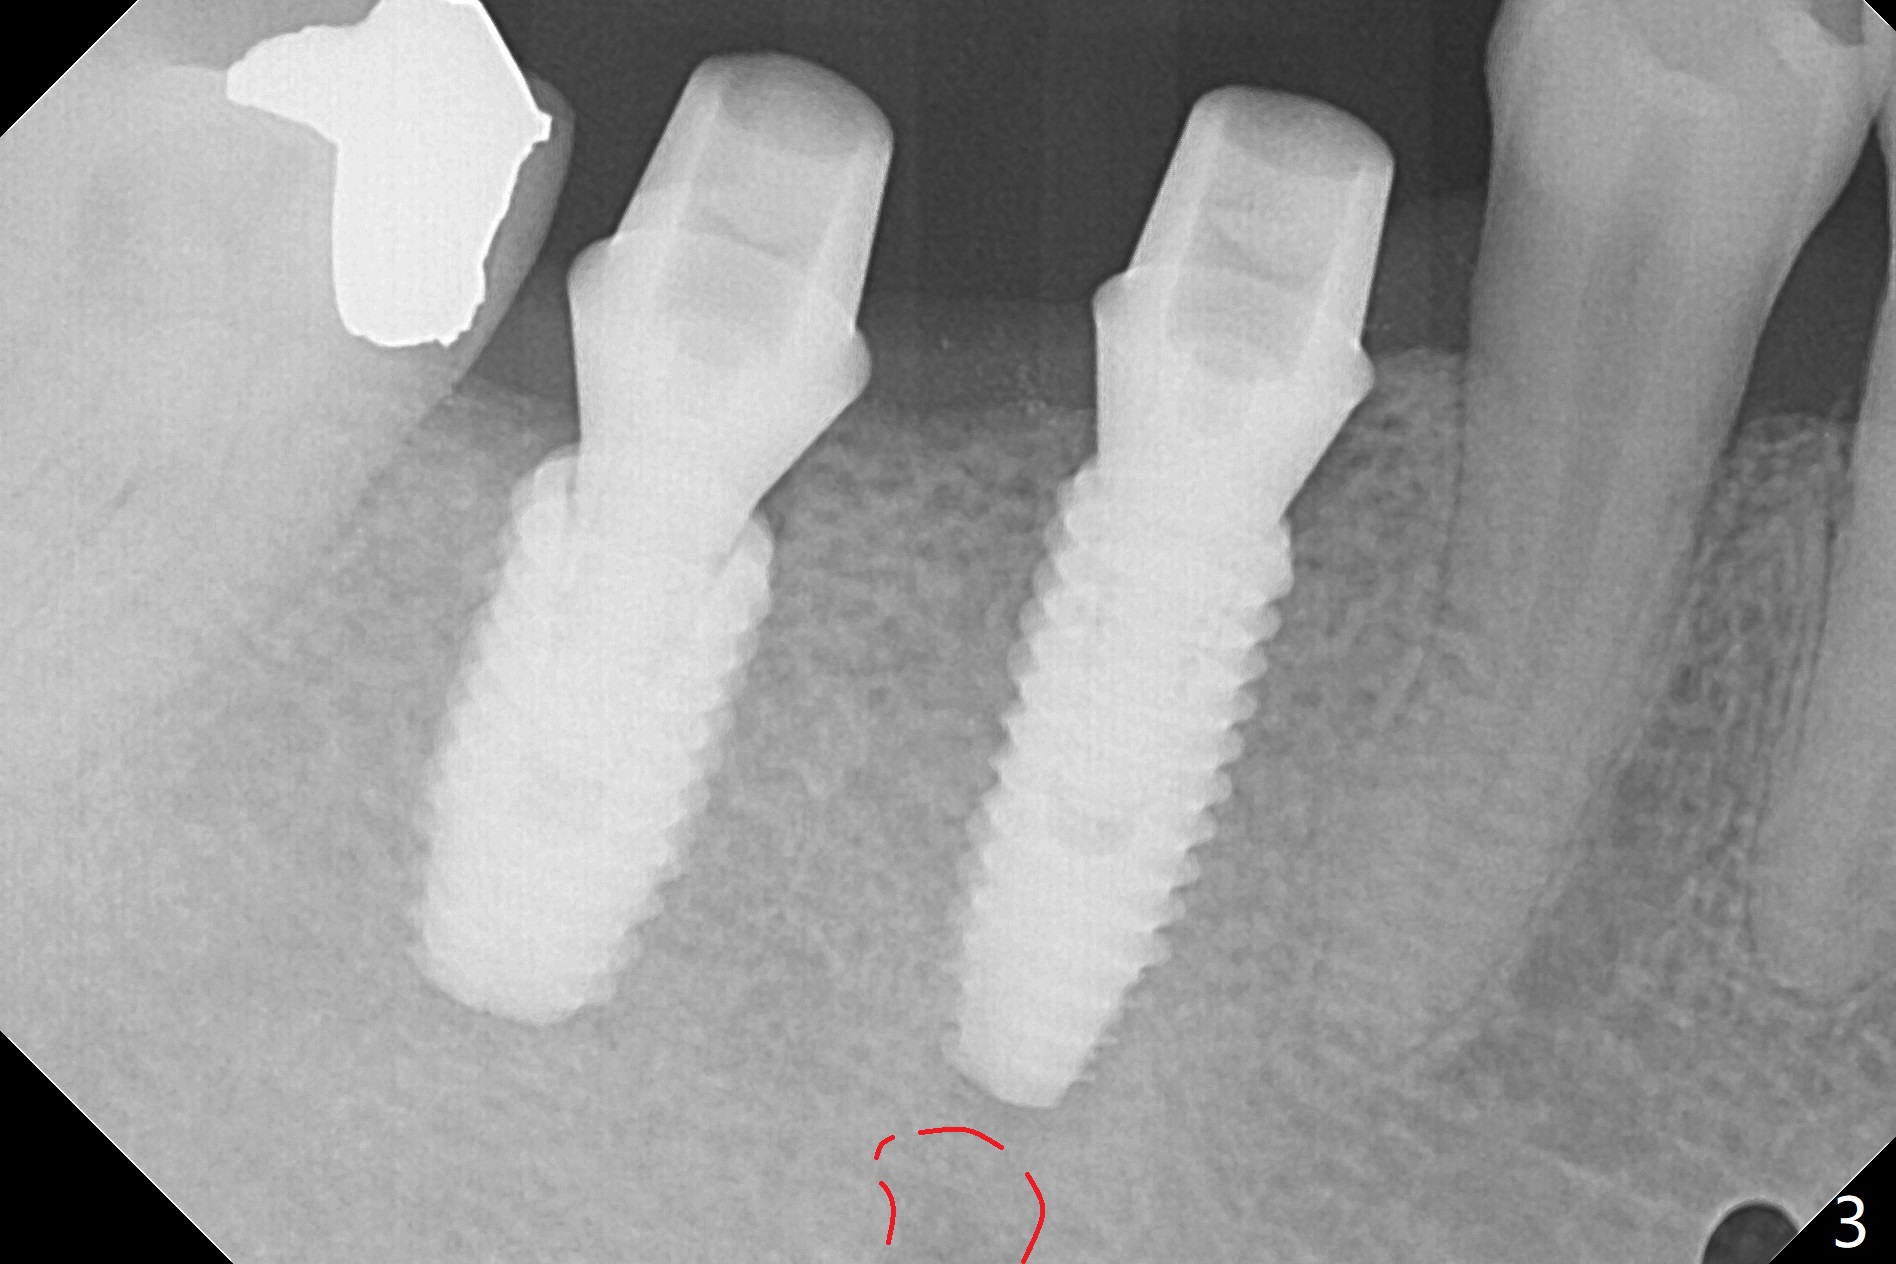

PA is taken after a 2.2 mm drill reaches depth of 11.5 mm with 10.5 mm offset at #29 to confirm that the curved apex of the neighboring tooth is not violated (Fig1 * (red line: Mental Loop)). The rest of the procedure is smooth except that the abutment at #29 is later changed to 4.5x4(4) mm (Fig.2,3 (red dashed line: Mental Loop)). The latter is easier for immediate splinted provisional and also has clearance from the crestal bone (Fig.5 *). Bone resorption seems to be minimal 4 months postop (Fig.4). The change in the abutment in cuff length (from 5.7x4.5(3) to (4) mm) at #30 eliminates the gag between the implant and abutment (Fig.4 <, as compared to Fig.5) before impression.